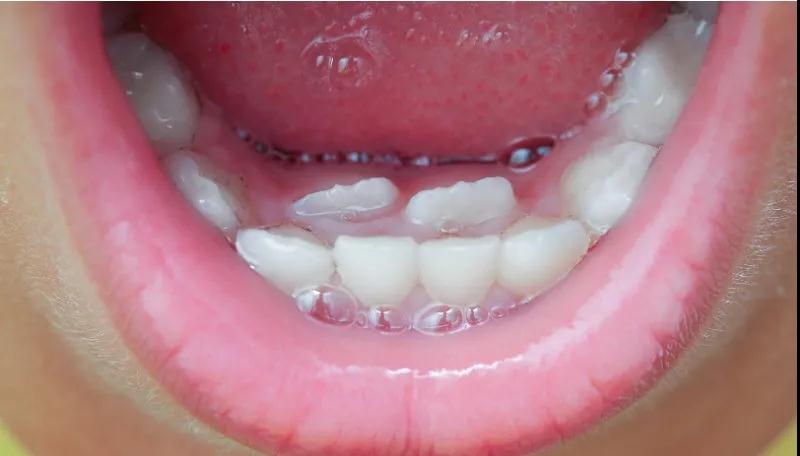

乳牙松动还没掉,新牙就长出来了怎么办?

A:首先家长需要认清的是,出现这种情况,与钙质太多可没有太大关系哦!

不能放任这种“双排牙”存在不管,这样会导致恒牙牙列不齐或颌骨发育异常,影响孩子牙齿整洁和形象。

家长也不要自己帮娃拔掉!这样牙齿极容易引起感染!应尽快请医生检查并拔除滞留的乳牙。